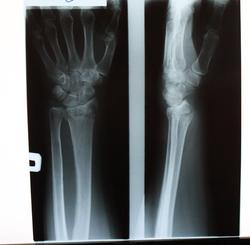

Пол пациента: Женский пол Тип патологии: Травма Область исследования: Скелетно-мышечная система Методы исследования: Rg Подскажите,пожалуйста,как правильно описать? ID:23973 Вс, 28/10/2012 - 16:21 #1 Dr.Yllich Не на сайте Был на сайте: 1 год 4 месяцев назад Зарегистрирован: 01.05.2011 - 22:52 Публикации: 1196 Вколоченный перелом луча в типичном месте со смещением тыльно на 1/5 диаметра и тыльным угловым. С уважением. Ильич. Вс, 28/10/2012 - 16:28 #2 Tis Не на сайте Был на сайте: 13 лет 9 часов назад Зарегистрирован: 23.10.2012 - 21:00 Публикации: 57 А шиловидный? Вс, 28/10/2012 - 16:31 #3 Андрей Юрьевич Не на сайте Был на сайте: 1 день 6 часов назад Зарегистрирован: 16.11.2008 - 22:16 Публикации: 18098 Р-признаки: оскольчатого внутрисуставного вколоченного перелома дистального метаэпифиза лучевой кости с угловым смещением отломков к тылу, плосткость эпифиза открыта к тылу под углом = ; повреждения дистального лучелоктевого сустава. Андрей Юрьевич Вс, 28/10/2012 - 17:34 #4 Любовь С. Не на сайте Был на сайте: 9 лет 5 месяцев назад Зарегистрирован: 23.12.2010 - 01:58 Публикации: 2324 Затрудняюсь сказать, что же снято... Полкисти и полпредплечья. В-общем, на рентгенограммах этого: оск. в/суст. пер. луча в т/м с разгибательной 200 (?) деформацией оси, незначит. боковым смещение отломков + перелом ШОЛК с/с. "Предоставляя весь смысл и совершенство в распоряжение одного только Бога, вы избавляете себя от бездны хлопот." Джон Уитборн. Вс, 28/10/2012 - 22:58 #5 Катенёв Валенти... Не на сайте Был на сайте: 7 лет 2 недели назад Зарегистрирован: 22.03.2008 - 22:15 Публикации: 54876 Обработанные снимки.Приложения:

Вколоченный перелом луча в типичном месте со смещением тыльно на 1/5 диаметра и тыльным угловым.

Р-признаки: оскольчатого внутрисуставного вколоченного перелома дистального метаэпифиза лучевой кости с угловым смещением отломков к тылу, плосткость эпифиза открыта к тылу под углом = ; повреждения дистального лучелоктевого сустава.

Затрудняюсь сказать, что же снято... Полкисти и полпредплечья.

В-общем, на рентгенограммах этого: оск. в/суст. пер. луча в т/м с разгибательной 200 (?) деформацией оси, незначит. боковым смещение отломков + перелом ШОЛК с/с.